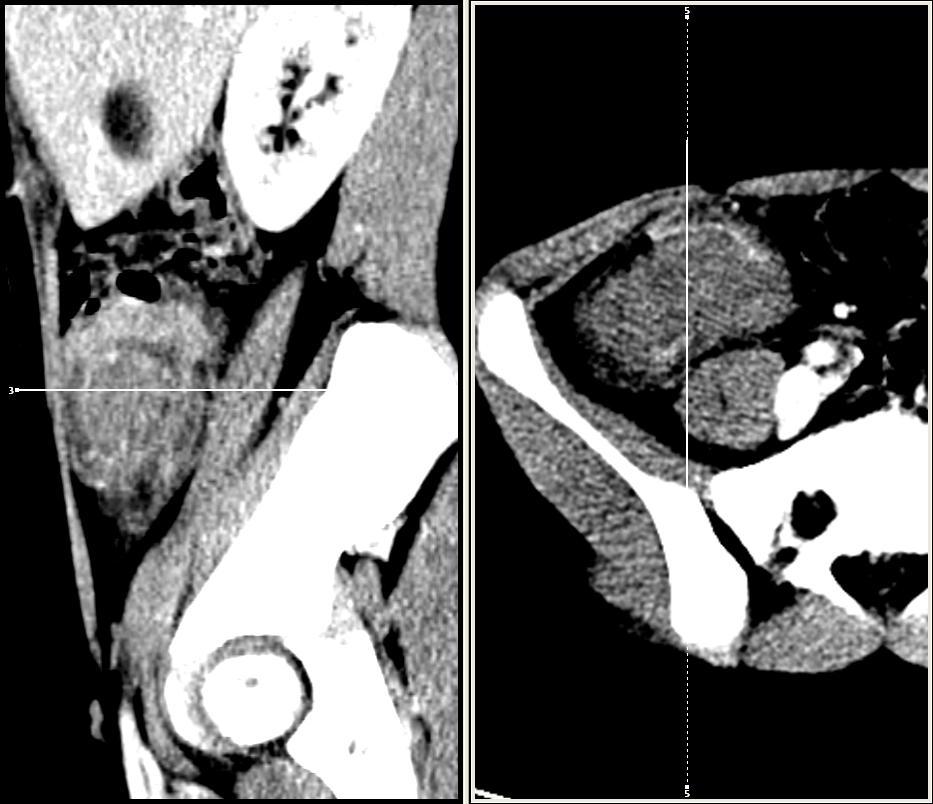

Ileocolic intussusception (leading point: colic Burkitt lymphoma) Szerző: admin | jan 2, 2012 | Colon cancer, Ileus, Invagination, Oncohaematology | Nincsenek hozzászólások 12 years old boy 3 days after surgical desinvagination; the leading point wascolon affected by Burkitt lymphoma 8302602012.01.02. – 400